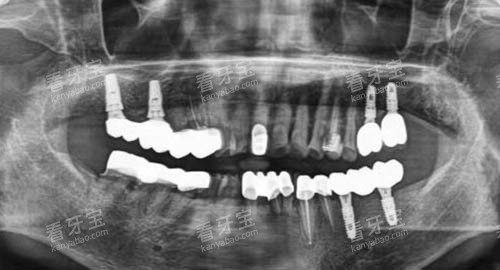

该口腔机构引进了国内外可靠的种植牙设备和技术,如智能化口腔 CT 设备、种植导航系统等。

智能化口腔 CT 设备能够为医生提供精细的口腔三维影像,帮助医生更更准地了解患者的牙槽骨情况,从而制定更合适的种植方案。

在手术前,医生们会对患者进行超全的口腔检查和评估,制定个性化的种植方案。

在手术过程中,医生们严格遵循手术操作规范,确保种植体的植入位置和角度更准无误。

在种植过程中,医生们会根据患者的牙槽骨情况选择合适的种植体,并采用可靠的种植技术将种植体更准地植入牙槽骨中。